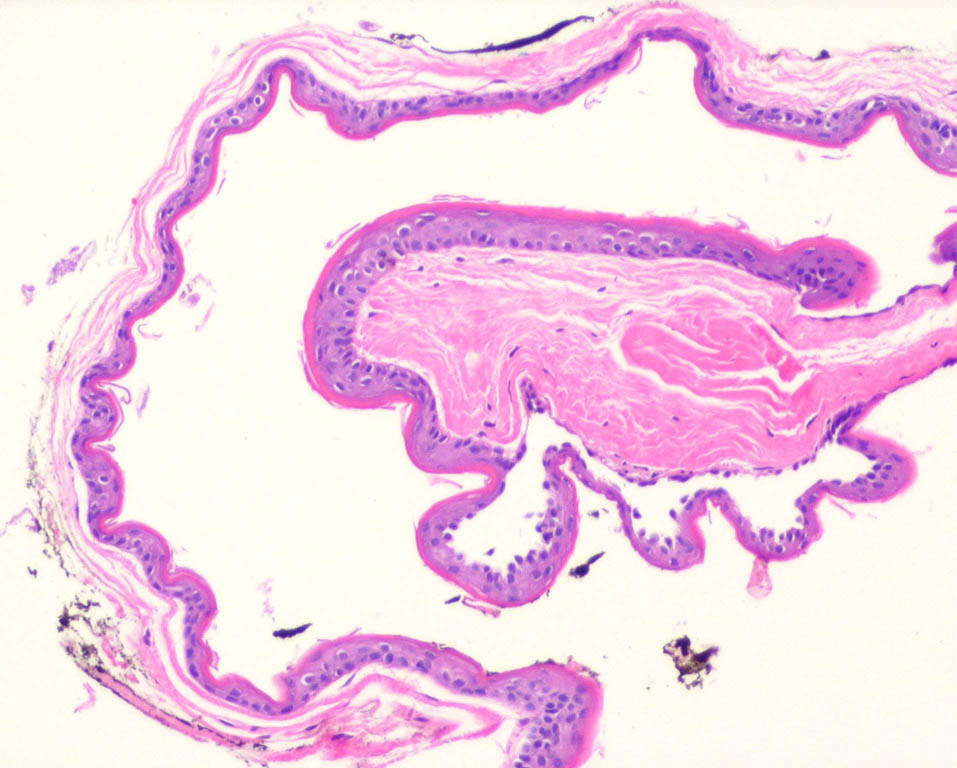

Steatocystoma =ورم كيسي دهني